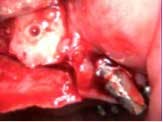

Under local anesthesia, a full thickness flap was elevated from the upper right to upper left posterior segments. Using a piezoelectric handpiece, a buccal window hinge osteotomy was elevated in the maxillary right posterior region. A mixture of DFDBA, anorganic bovine bone, and PRF was placed. A collagen membrane was used to cover the buccal window. Simultaneously, two puros J-block allografts were secured in the 5 to 7 and 10 to 12 region with stainless steel screws (1.6 x 8 mm screws). A mixture of DFDBA, anorganic bovine bone and PRF was placed over each area and covered with PRF sheet and a collagen membrane. Primary closure was obtained with CV-5 Goretex sutures. Healing was uneventful. After six months of healing, six straight implants were placed in sites 3, 4, 5, 6, 11, and 12. Healing abutments were placed at stage I. Healing was uneventful. After four months of healing, six custom abutments were fabricated by his dentist and cover screws were placed on implants 8 and 9 and converted into pontics.

Case 2: Sinus lift, bone graft, PRP, and after healing implant placement